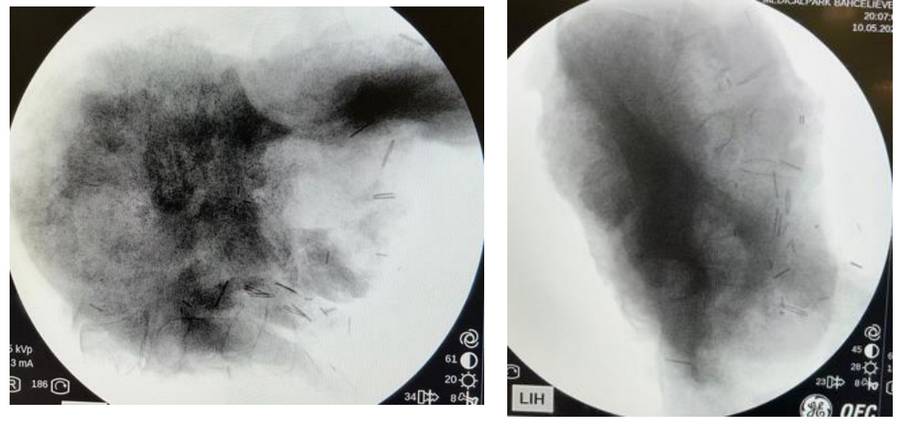

During the operation: Fluoroscopy image of the removed tumor tissue.

Post-operative: Seen on X-ray after resection.